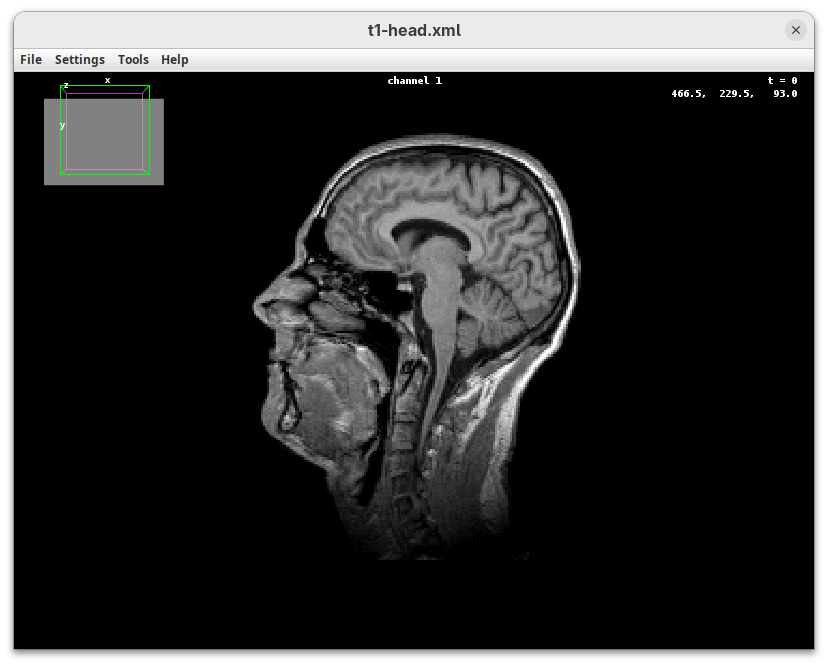

BigDataViewer (Pietzsch et al. 2015) is one of the most important tools for visualizing large, multidimensional datasets. It provides a simple and intuitive interface and shortcuts to swiftly navigate through your sample even on a regular laptop. This is possible because of the underlying file format used by BigDataViewer: the XML/HDF5 combo. Therefore, before opening the plugin, we must convert our dataset.

The BigDataViewer interface will open showing an optical section of the head sample.

Getting familiar with BigDataViewer is an essential skill for navigating large 3D datasets. It’ll also be important for the multiview registration pipeline. So, take the time to learn the basic commands and shortcuts. It is nicely intuitive. The BigDataViewer’s page on the ImageJ Docs has the official documentation and we can also go to Help > Show Help for an up-to-date overview.

Some of the movements to try:

Left-click and drag: turn the sample around the mouse pointer at any arbitrary angle.Right-click and drag: move the sample in the XY plane (of the view).Scroll: move through the Z plane (of the view). UseShift+Scrollto move fast.Ctrl+Shift+Scroll: zoom in or out.

But, most importantly, are the commands to put your sample back to its original orientation or along any of the original dimension axes:

Shift+Z: orient the sample on the XY plane.Shift+X: orient the sample on the ZY plane.Shift+Y: orient the sample on the ZX plane.

Finally, a visual tip. The default interpolation between image slices is nearest-neighbors. Press I to activate the tri-linear interpolation to obtain a much smoother (and improved) data visualization.